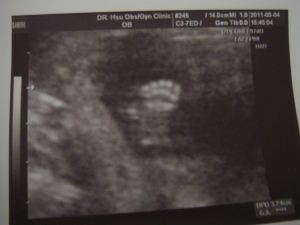

(孫寶寶 15.5 禮拜,可愛的小腳丫 )